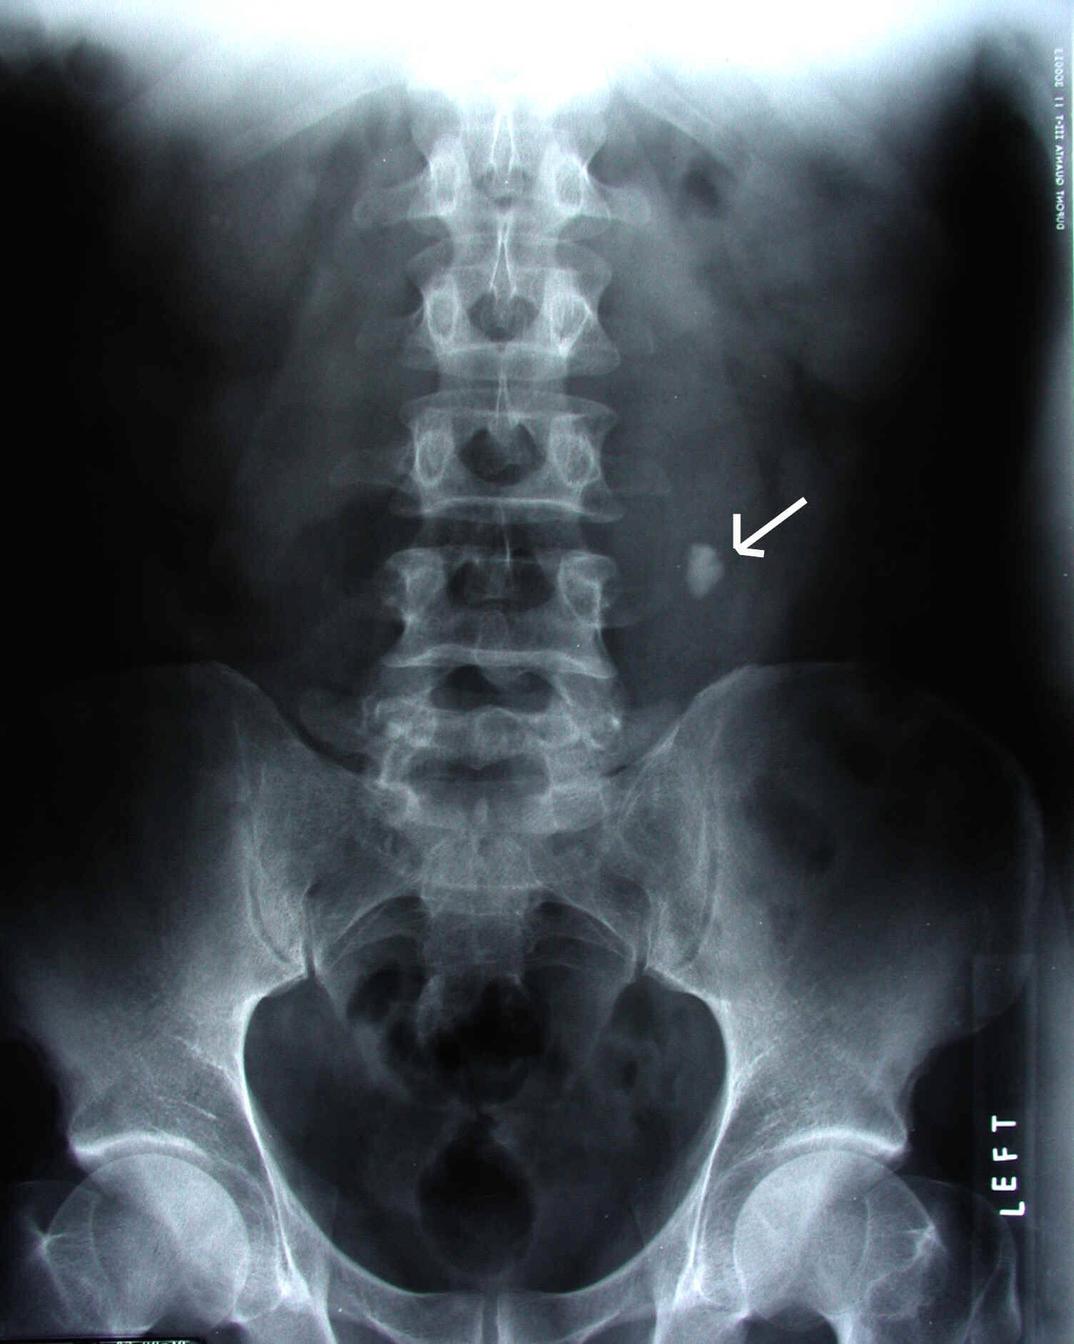

pediatrickidneystoneCT How Long Is Too Long For A Kidney Stone To Pass Small stones (less than 4 mm) usually pass on their own in about 31. How long does it take to pass a kidney stone? How long it takes to pass a kidney stone depends on how big it is. That depends on the size of the stone and where the stone is located. Size is a determining factor in whether. How Long Is Too Long For A Kidney Stone To Pass.